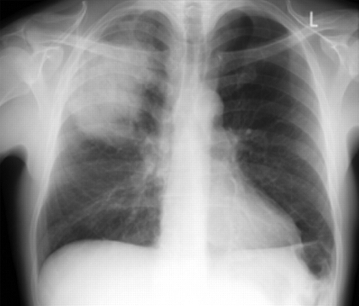

Radiografia de tórax posteroanterior mostrando consolidação do lobo superior direito em um paciente com pneumonia adquirida na comunidade

Durrington HJ, et al. Recent changes in the management of community acquired pneumonia in adults. BMJ 2008;336:1429.